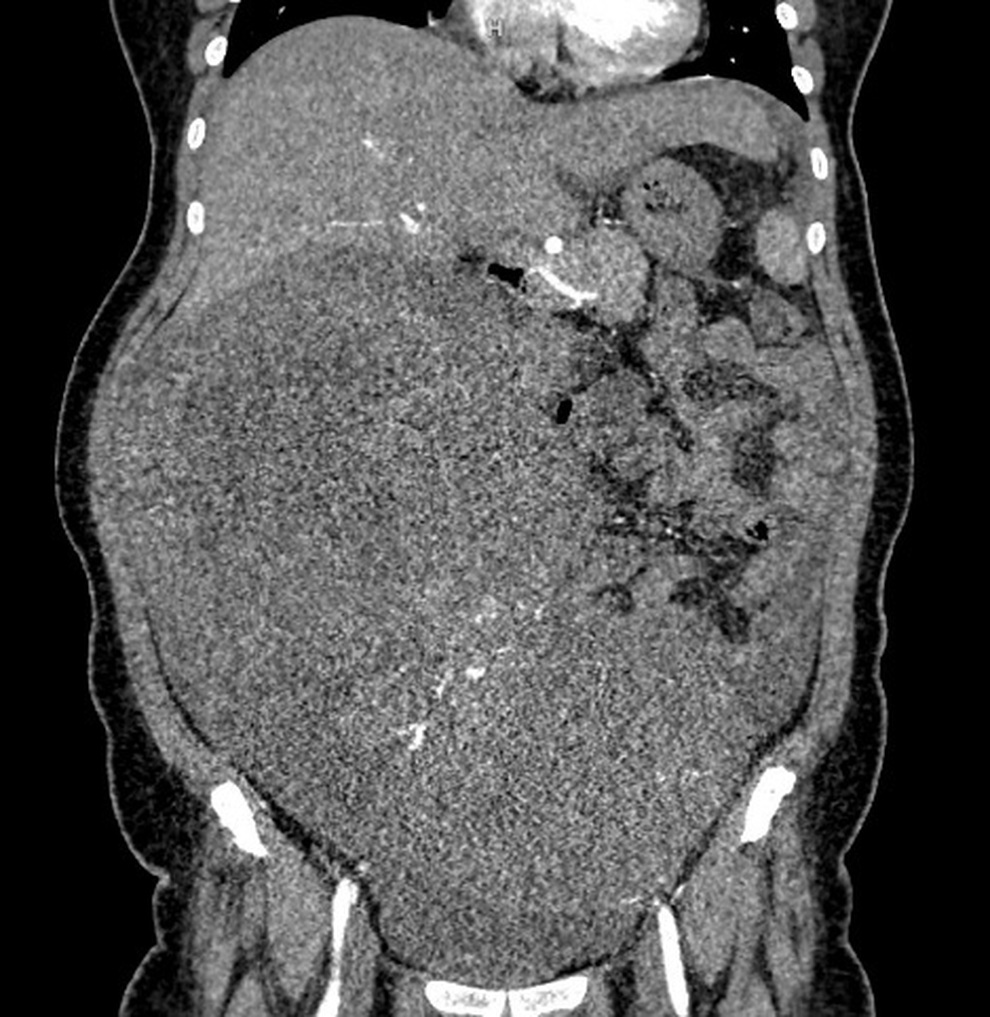

Hình ảnh phim chụp cho thấy khối u chiếm toàn bộ ổ bụng, chèn ép các tạng xung quanh (Ảnh: Bệnh viện cung cấp).

BSCKII Lê Văn Thành, Phó Giám đốc Bệnh viện Ung Bướu Hà Nội, Trưởng khoa Ngoại Tổng hợp cho biết, hình ảnh chụp cắt lớp vi tính cho thấy khối u lan tỏa vùng hạ sườn phải, quanh rốn và hạ vị với kích thước lên tới 22,7x29cm.

Khối u tiếp xúc và chèn ép nhiều cơ quan như gan, túi mật, thận phải, tụy, đồng thời dính với đáy tử cung. Ngoài ra, bệnh nhân còn có tình trạng dịch ổ bụng nhiều và tràn dịch màng phổi hai bên.